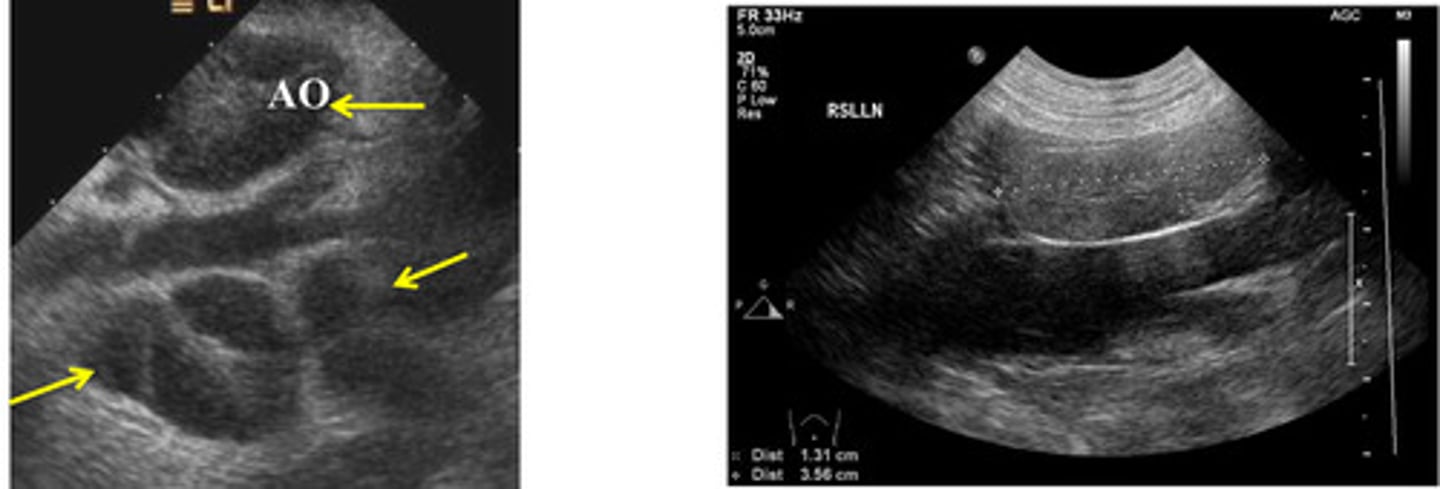

ID lymph node

medial iliac lns.

ID lymph node (hint: trifurcation near)

jejunal lns.

what are these lns.?

which lns. are these?

left- neoplasia

right- normal/reactive

which medial iliac ln. is neoplastic and which is normal/reactive?

lymphoma

which abnormality is this?